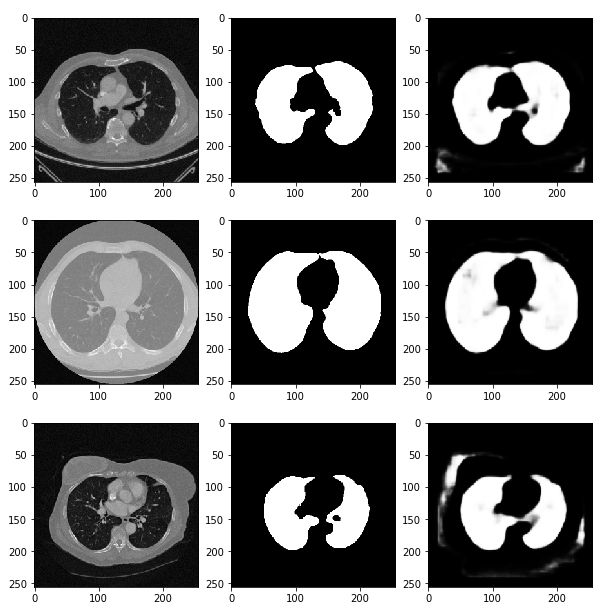

preds = model.predict(x_val) # predict 함수를 통해 (x_val) 검증한다

fig, ax = plt.subplots(len(x_val), 3, figsize=(10, 100))

for i, pred in enumerate(preds):

ax[i, 0].imshow(x_val[i].squeeze(), cmap='gray') # 첫 번째 열에는 CT 데이터(x_val[i])를 삽입

ax[i, 1].imshow(y_val[i].squeeze(), cmap='gray') # 두 번째 열에는 정답 데이터를 넣는다.

ax[i, 2].imshow(pred.squeeze(), cmap='gray') # 세 번째 열에는 우리가 예측한 결과값을 그려본다.

# 이러한 딥러닝을 활용하여 산소의 수치, 적혈구, 백혈구의 농도 등 수치적 데이터를 가지고 예측하는 방법도 존재함.